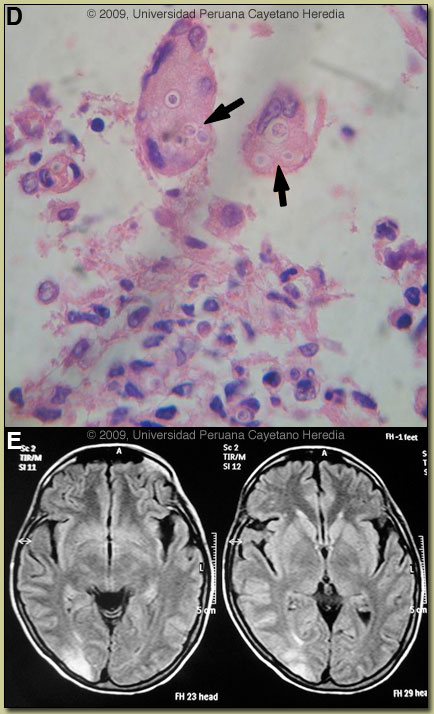

Discussion: A biopsy of a colonic ulcer disclosed a dense chronic inflammatory reaction with granuloma formation and intracellular yeast forms within multinucleated giant cells [Image D, arrows]. No cultures were done at the time of biopsy but subsequent stool culture (+) for P. braziliensis. Further work-up of the lung lesion is pending. HTLV-1 (+); no association between HTLV-1 and paracoccidioidomycosis has been reported despite both agents being common in many areas of Brazil.